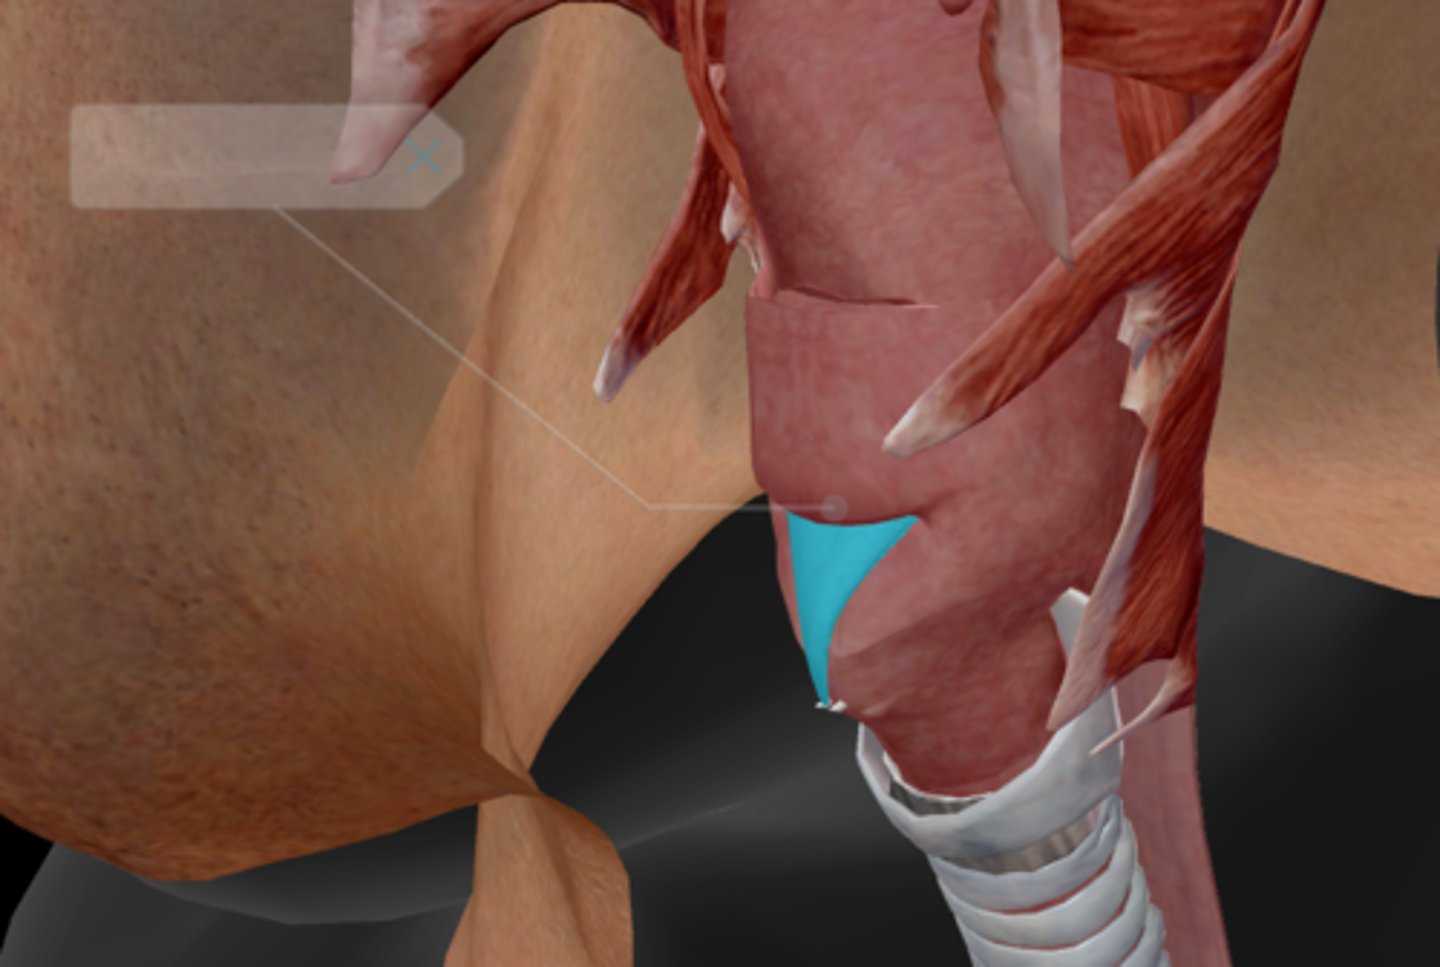

Larynx

Epiglottis

Thyroid cartilage

Cricoid cartilage

Arytenoid cartilage

Corniculate cartilage

Vocal ligament

Vocal folds

Vestibular folds

Trachea

Tracheal cartilaginous rings